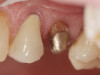

Case 1

A Class IN maxillary bicuspid was previously restored with a fiber post and an all-porcelain crown (Figure 1). The forces of the oral environment resulted in fracture of the fiber post and crown failure. The remaining fiber post in the root was removed, and anti-rotational areas were prepared for a cast post (Figure 2). A gold cast post was constructed at a dental laboratory, using an indirect technique (Figure 3). A porcelain-fused-to-metal (PFM) crown was constructed with a bevel finish to provide a ferrule and reduce forces on the post (Figure 4 and Figure 5).

Figure 3  Cast post to restore the second bicuspid.

Figure 3